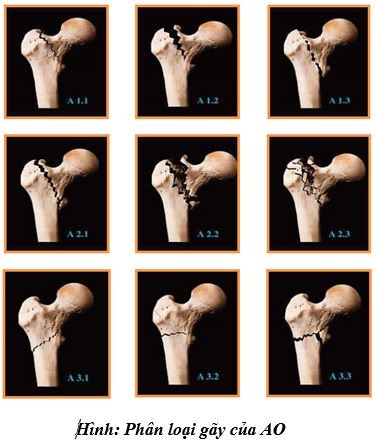

3. Phân loại AO

Các tác giả AO chia liên mấu chuyển xương đùi thành 3 nhóm chính A1 – A2 – A3; trong mỗi nhóm chính lại có 3 tiểu nhóm: A1.1; A1.2; A1.3;…

- Loại A1: Loại gãy đơn giản có một đường gãy chạy từ mấu chuyển lớn đến vỏ xương bên trong gồm 3 dạng sau:

- A1 – 1: Đường gãy nền cổ mấu chuyển.

- A1 – 2: Đường gãy liên mấu chuyển

- A1 – 3: Đường gãy dưới mấu chuyển bé.

- Loại A2: Loại gãy mấu chuyển có nhiều mảnh rời hướng đường gãy được xác định giống loại A1 nhưng vỏ thân xương bên trong gãy thành 3 mức.

- A2 – 1: Gãy có một mảnh rời.

- A2 – 2: Gãy có 2 mảnh rời.

- A2 – 3: Gãy có nhiều hơn 2 mảnh rời.

- Loại A3: Đường gãy chạy từ vỏ thân xương đùi ngay dưới mấu chuyển lớn chạy vào trong mấu chuyển bé, nếu đường gãy bên ngoài bắt đầu từ dưới mấu chuyển lớn kết thúc bên trong trên mấu chuyển bé thì loại gãy này cũng được xếp vào nhóm A3 (đường gãy chéo ngược)

- A3 – 1: Đường gãy đơn giản (chéo, chếch lên)

- A3 – 2: Đường gãy đơn giản (ngang)

- A3 – 3: Gãy A3 – 1 có kèm gãy mấu chuyển nhỏ.

Ý nghĩa lâm sàng của phân độ gãy liên mấu chuyển xương đùi theo AO:

- A1: Là loại gãy vững dễ nắm chỉnh.

- A2: Là loại gãy không vững, đặc biệt là A2 – 3.

- A3: Là loại gãy rất không vững, dễ di lệch, khó nắn chỉnh, hay di lệch khép.